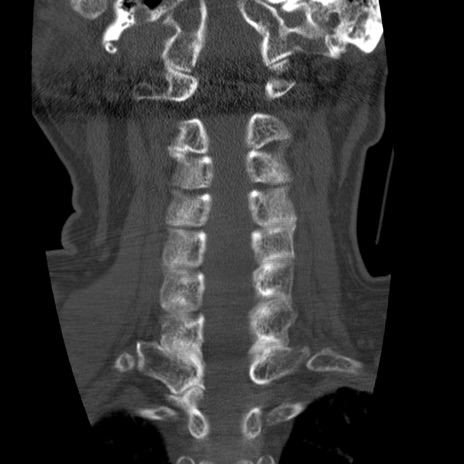

症例50 頚椎CT(冠状断像)

頚椎CT